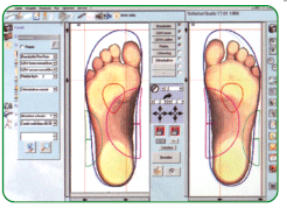

Fußvermessung

Wir vermessen für Sie Computer

genau!

Mit modernster Computertechnik können wir mit

einem Scanner ein genaues Abbild Ihrer Füße in ein

Computerprogramm übertragen und so die Fußform,

die Belastungspunkte und die Schuhgröße

bestimmen und bewerten.

Aufgrund der hier gewonnenen Erkenntnisse lassen

sich passgenaue Schuhe finden und entsprechend

Ihrem Fuß zurichten.

Auch Einlagen und Maßschuhe werden

nach diesen Daten individuell angefertigt.

Bei der Schuhinnendruckmessung lassen sich die

real wirkenden Kräfte zwischen Fuß und Schuh in der

Statik und Dynamik mit einer leicht verständlichen

Darstellung erklären. Diese Daten sind besonders bei

einer Neurophatie sehr hilfreich um Druckstellen zu

erkennen und zu beheben.

Computeranalyse

Mit Hilfe eines Scanners werden ihre Füße

abgelichtet und vermessen, auch die Beinachse

wird hierbei beachtet.